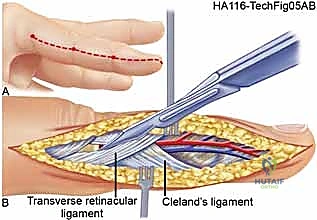

The carpal tunnel, while technically not a muscle compartment, is a critical closed space at the wrist that must be released during volar forearm decompression to prevent median nerve strangulation. In the digits, the fascial anatomy is defined by Cleland’s and Grayson’s ligaments, which compartmentalize the volar and dorsal aspects of the fingers. The limited compliance of the digital skin means that even minor fluid accumulation can lead to digital ischemia, necessitating prompt mid-axial release.

For the digits, mid-axial incisions are placed on the non-contact borders (ulnar border of the index and middle fingers; radial border of the ring and small fingers).

The incision is carried down through the skin and subcutaneous tissue.

The dissection must divide Cleland's and Grayson's ligaments to fully decompress the digital compartments while carefully protecting the neurovascular bundles lying volar to the mid-axial line.